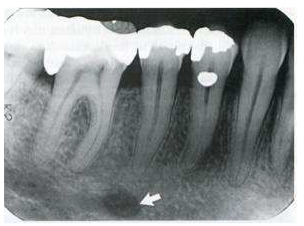

64.下圖根尖片中白色箭頭所指位於右下顎第二小臼齒根尖部位之橢圓形放射線透過性(radiolucent)影像,最可 能為下列何者?(A)Radicular cyst(B)Lingual foramen(C)Mental foramen(D)Apical scar